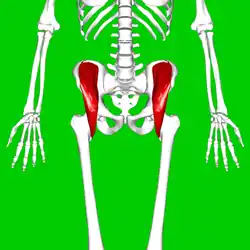

Position of iliacus muscle (shown in red.) | |

Position of iliacus muscle (shown in red.) Animation.